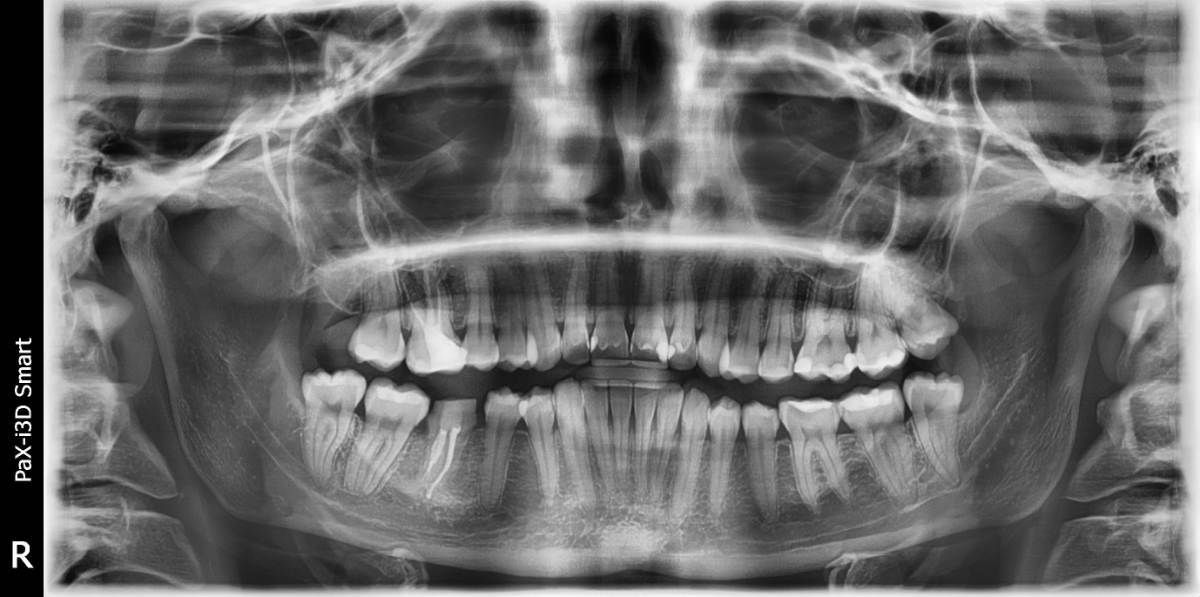

Снимок сразу после операции

CODREANU_POST_OP_1_YEAR.jpg.4d431f001aa21f3bdfff9e1f24e57adf.jpg

Панорама через год

Через год пациентка пришла на протезирование, периотест -1/-3 и панорамка тоже с признаками анкилоза (я связку не вижу).

Кандидатами на трансплантацию были только 1.8 и 2.8, к сожалению длина корней обоих нижних моляров не позволяла уместить их не задев нижнечелюстной канал (это в целом видно и по панорамному снимку